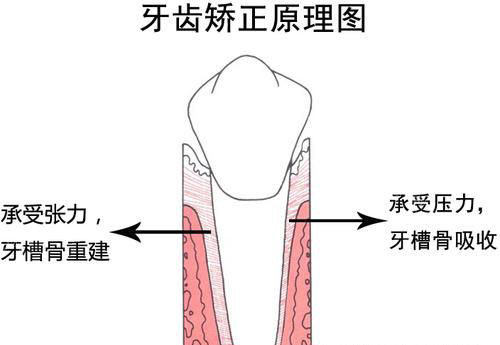

科室业务范围涵盖牙体牙髓病、牙周病、口腔黏膜病、口腔颌面外科、口腔预防、儿童口腔、口腔修复、口腔正畸、口腔种植科等。在意运用中西结合方法治疗口腔疾病,如牙周病、粘膜病等,颇具特色。